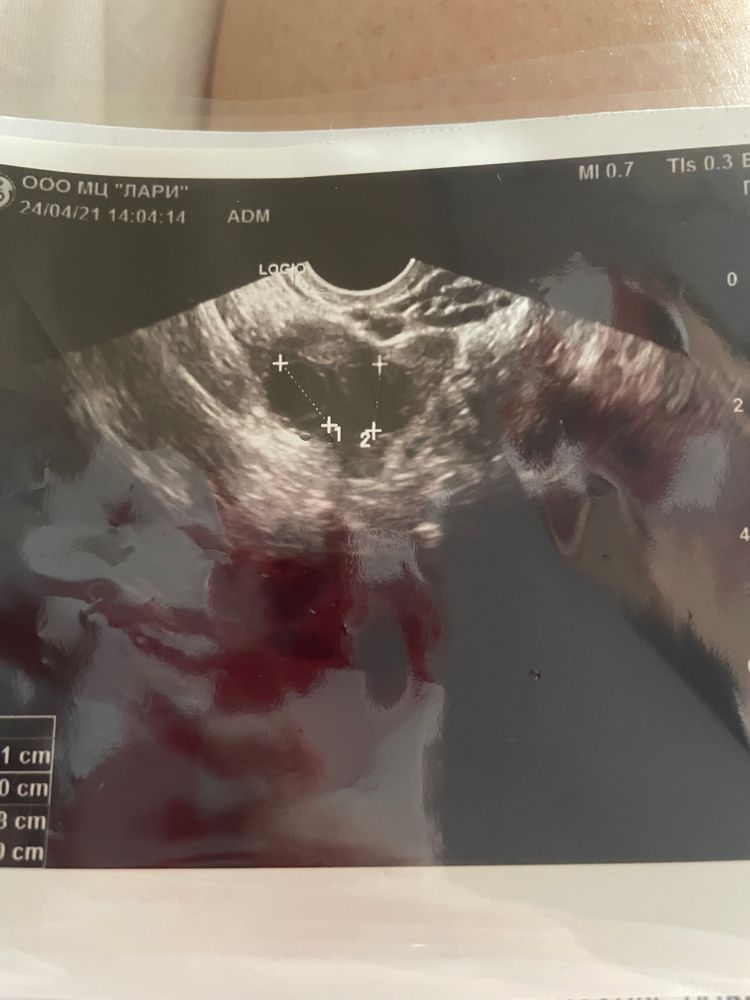

Два доминантных фолликула

Мария, я думала прогик второй фазы подавит овуляцию 🙄 спасибо 🌺 ох на двойню даже не смею надеятся. Вообще удивительно что так созрели два фоллика . Я без стимуляции обычный цикл , вот такое сердечко было на узи 🐣🐣